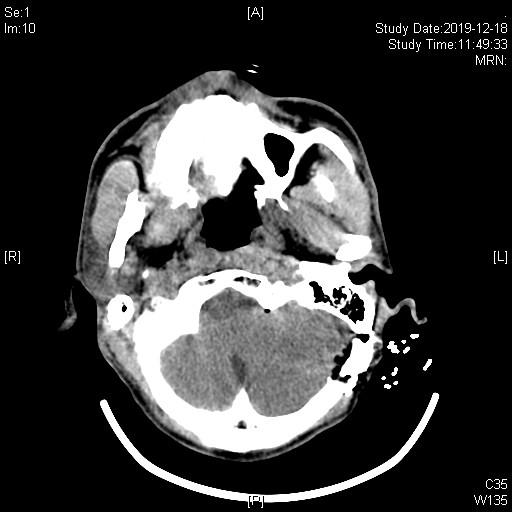

术后复查CT术区无出血,患者手术后立即停跳。